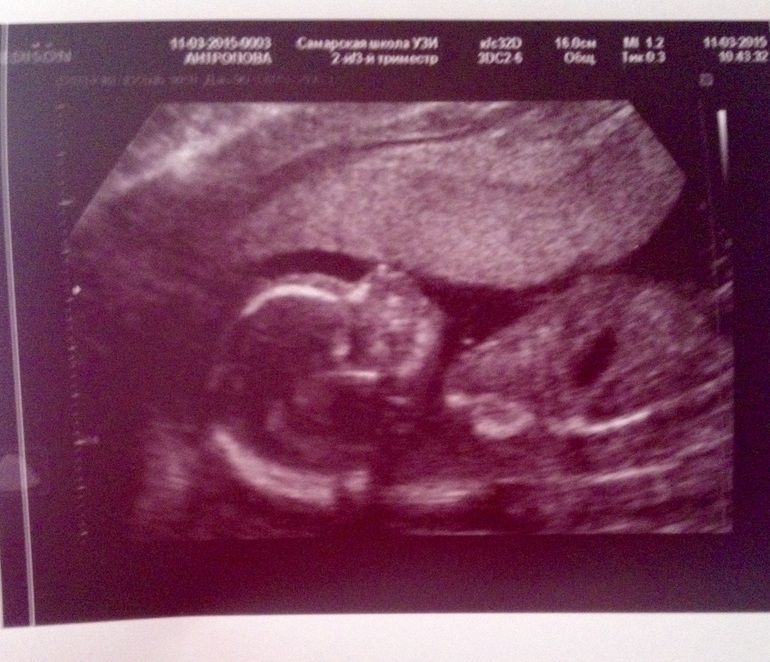

Вот вот и у нас такие же щекотульки в животе))) и изредка уверенные пиночки. Рано еще тем более что у нас плацента по передней стенке, с ней сложнее шевеления почувствовать! Ну ничего, всему свое время))) я думала малыш еще меньше, а он уже аш 227 грамм весит🐘🐘🐘)))) могу вам только нашего показать)) у вас примерно тоже самое))) 6d6c8a50f607887aede77c20def85b0a.jpg

in_love.gifкакой пузатик!!! Ой какой милый! ТТТ, что б не сглазить (хотя я за собой этого не замечала!). Аручки вдоль тельца вытянул?

Ну в момент фото да, а до этого левую около лица держал, а правую вверх вытягивал!))) и ноги то скрещивал то вытягивал ))) муж говорит "и как ты все это не чувствуешь"!))))